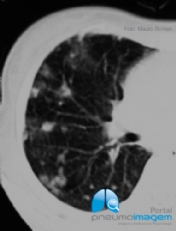

CASO CLÍNICO #52

Paciente do sexo feminino, 46 anos, submetida a transplante de medula óssea há 2 meses, apresenta-se com dispneia, tosse seca e dessaturação. Qual o provável diagnóstico? Deixe seus comentários abaixo! ***** A 46-year-old female patient who underwent bone ma...